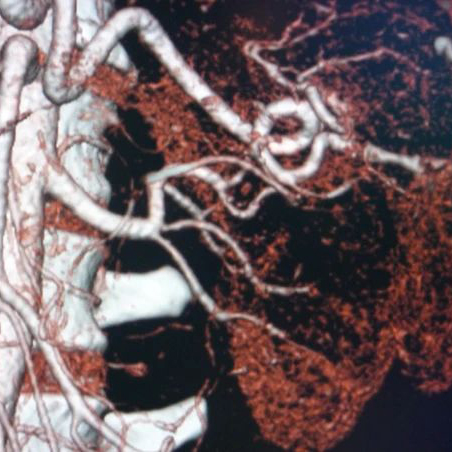

VASCULAR ANOMALIES OF THE KIDNEY

Crossing vessel at PUJ

Vascular malformations of the kidney are disease processes that involve renal veins and arteries and include congenital arteriovenous malformations (AVMs) and arteriovenous fistulas. AVMs are congenital communications between arteries and veins with a vascular nidus that bypass the capillary bed.